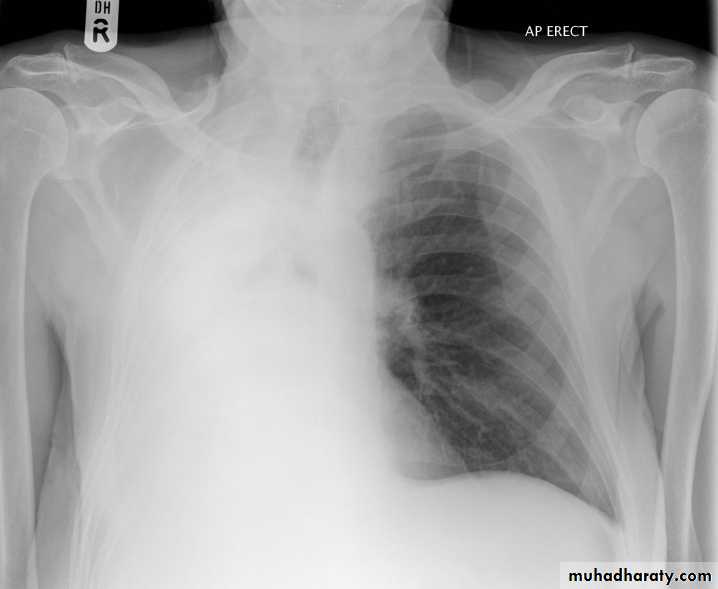

Tension pneumothorax

56.tension pneumothorax left sided aspect

57. tension pneumothorax right sided aspect